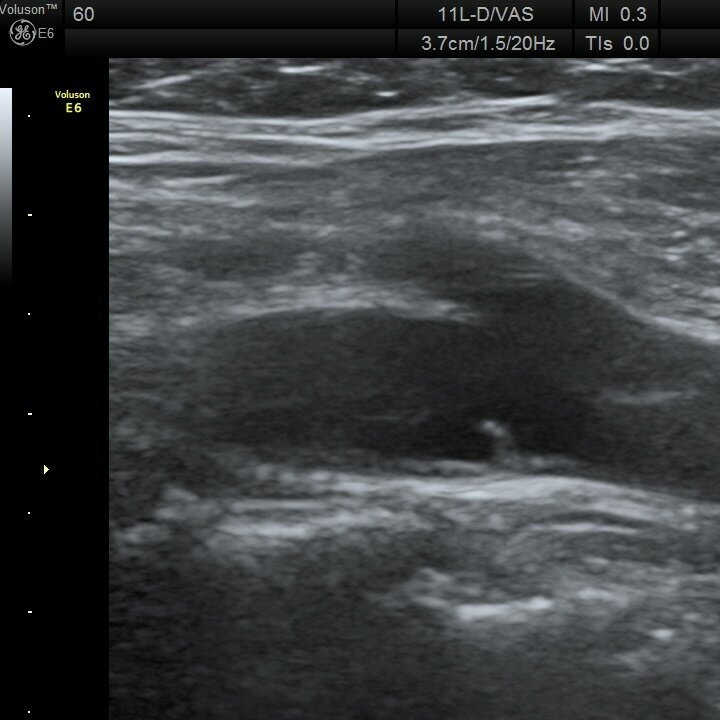

Бляшка с покрышкой

🖼️Типичная картина "Бляшка с покрышкой". Внутри бляшки происходит кровоизлияние, в итоге эхогенность соответствует просвету артерии. При этом видна наружная яркая часть - капсула, она же "покрышка".

👨‍💻Такая находка - бомба 💣 с часовым механизмом. При повреждении покрышки развивается тромбоз и эмболия в артерии мозга. Как итог - инсульт.